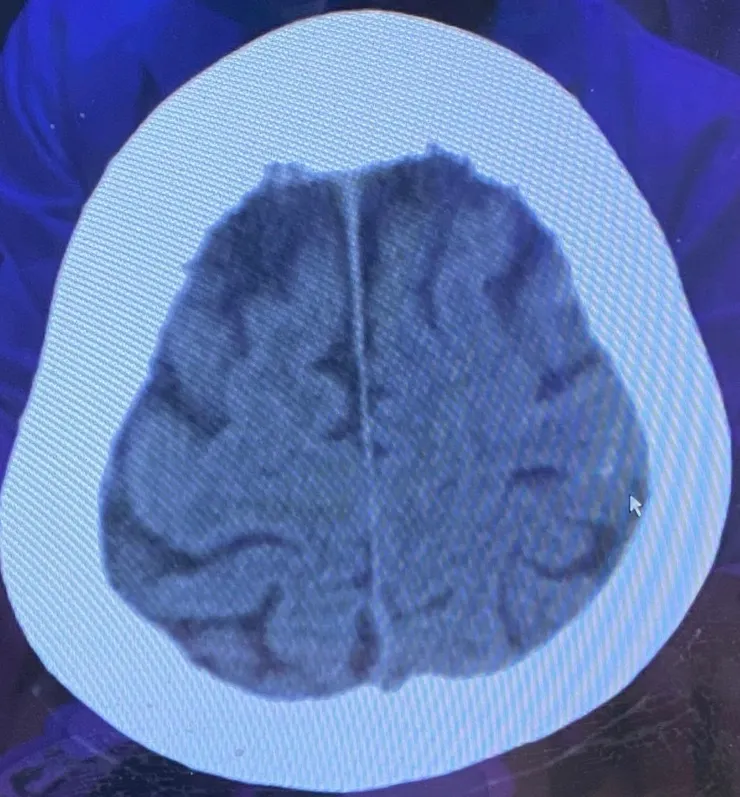

即將邁入老人身份的你,在這天突然發生車禍,現場昏迷被送到急診室裡。檢查出有腦震盪和腦出血!直到做完CT後你才甦醒過來,出事的過程你全然無知…